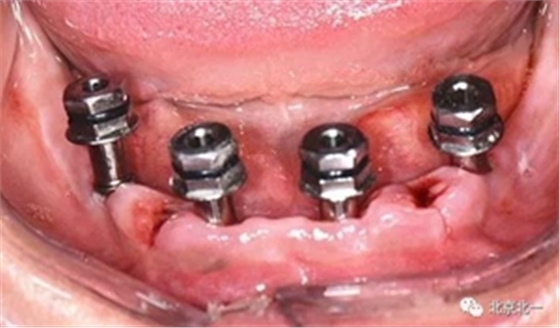

圖十四:口內(nèi)照

圖十六:術(shù)后三個月永久修復(fù)取模,夾板固定。